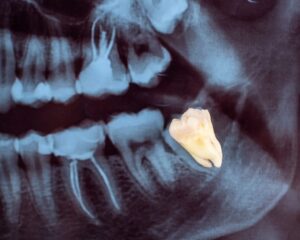

A dental exam reveals wisdom tooth positions through x-rays and thorough checking. Your dentist spots decay, infections, or cysts before they cause serious problems. Early treatment prevents nerve damage and stops infection from spreading to other areas.